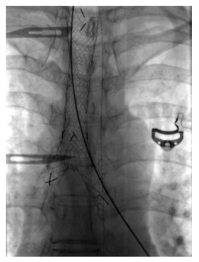

In January 2017, she presented with two- week history of worsening of shortness of breath, wheeze and stridor. Further evaluation showed interval increase in circumferential thickening of trachea and bilateral main stem and lobar bronchi on HRCT of the chest and neck. However, repeat ANCA was negative for both proteinase 3 and MPO by line immunoassay and by indirect immunofluorescence for cytoplasmic and peri-nuclear ANCA. After initial treatment with broad-spectrum antibiotics and increased steroid dose, she had a marginal improvement. Considering this as a disease relapse, she was given rituximab 2 g two weeks apart. At subsequent follow-ups, the patient was doing well with just oral prednisolone 5 mg daily. At fourth month follow-up, HRCT of the chest with neck cuts was repeated and it showed reduction in wall thickening as compared to the previous scans (Figure 2). This time, the patient was given early rituximab 500 mg maintenance therapy and discharged on same dose of oral prednisolone and cotrimoxazole.